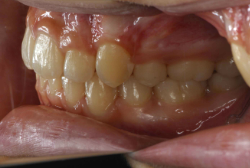

「歯並びの凸凹を直したい」という主訴で来院したケースです。診断の結果、たしかに「叢生」という隙間が足りないと言うことが原因の凸凹症例でした。

しかし、それ以上に問題なのは「前歯の噛み合い方が深すぎる」という症状で、初診の歯の正面写真を見ると下の前歯が全く見えません。こういう症状を矯正学では「過蓋咬合(かがいこうごう)」と言います。過蓋咬合を放置すると、将来的に顎関節に悪影響を与えるとされており、顎関節症の原因因子の一つです。また下の前歯の先端が、上の前歯の裏側の歯茎と強く接触するため、歯周病の原因にもなります。

検査の結果、凸凹が軽症なため非抜歯で矯正すること可能と判断、マルチブラケット装置にて治療しました。治療後は歯並びが綺麗になっただけでなく、噛み合わせ的にも正しい状態が確立しています。